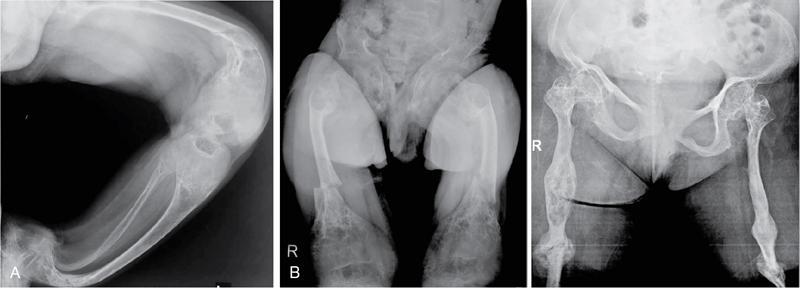

MISCELLANEOUS PAEDIATRIC RADIOGRAPHY – TECHNIQUES AND INTERPRETATION: SKELETAL SURVEY Padma V. Badhe The skeletal survey, generally performed in children, is a set of radiographs done in order to evaluate the entire skeleton. A skeletal survey, commonly used to evaluate skeletal dysplasias, acquired metabolic disorders and suspected child abuse, is still the key radiological investigation for the same. Hence, an explicit understanding of the technique along with the common disorders forms the basis of making a diagnosis in these paediatric pathologies. A skeletal survey is done for various skeletal dysplasias, non-accidental injury (battered baby syndrome) and suspected child abuse. It can also be done in cases of metabolic bone diseases, disseminated infections, multiple myeloma, eosinophilic granuloma. It is also used in evaluation of metastatic bone diseases and polyarticular arthropathy. Orthogonal views of the skull, spine, pelvis and one extremity are taken, preferable in standing position. For preterm babies/newborns, AP and lateral views of babygram may be taken. Projections: For skeletal dysplasias: Additional views: Both extremities may be taken if epiphyseal abnormalities and limb asymmetry is present. Focused views for specific pathologies may be taken. When a diagnosis remains uncertain, 1 year follow up is usually recommended. For preterm babies/newborns: AP and lateral views of babygram may be taken with additional specific views for extremities. For suspected non-accidental injury (NAI): AP and oblique view of chest is taken for better evaluation of the ribs. AP view of abdomen with pelvis. Both upper and lower limbs are evaluated. In lower limbs, two projections in AP and lateral (one with both femur including hip and knee joints; and another for foot and ankle) is taken. AP and lateral views of whole spine, skull. Oblique view of hands. A babygram should be avoided in cases of NAI, as subtle fractures are easily missed. Proper legal documentation while taking the views is very important and ideally two health care professionals must be present. For metabolic disorders: entire skeletal survey is usually not required. Specific views of hands, knees and spine may be taken with additional views depending on the suspected pathology. Centring point: Varies according to the part being examined. Angulation, collimation and orientation: Varies according to the part being examined. Images must be well collimated to obtain lower radiation dose. Detector size: Varies according to the part being examined: 8″ × 10″, 10″ × 12″, 11″ × 14″. Exposure: Ideally high kVp images are taken to reduce radiation dose. But in suspected NAI, low kVp/high mA images are recommended to better demonstrate findings. SID (Source Image Distance):100 cm Grid: Grids are not routinely used to image spine, pelvis, skull and abdomen in children. Radiation dosage: 0.3–3 mSv Essential image characteristics: Adequate spatial resolution, high signal to noise ratio, low kVp (50–70) for high contrast should be done. Excellent bone and soft tissue details are required. The presentation of skeletal dysplasia can range anywhere from minimal stunting of growth and bowing of limbs to severe dwarfism and multiple fractures. Knowledge of the commonly encountered dysplasias with an approach to arrive at a diagnosis is vital in any Radiologist’s practice The following flow chart summarizes the classification of important skeletal dysplasia: The following table summarizes the various dysplasias affecting the axial skeleton: TABLE 7.5.1.1 The following flow chart summarizes the working approach to skeletal dysplasias: Osteopetrosis (Albers-Schonberg disease/Marble bone disease) (Fig 7.5.1.1): Osteopetrosis clinically presents with anaemia/thrombocytopenia or cranial nerve compression. Radiological features include generalized increase in bone density with loss of medullary space. However, cortico-medullary appreciation with cortical thinning is also rarely seen. Bone within bone appearance with Erlenmeyer flask deformity is also noted. Pyknodysostosis (Figs. 7.5.1.2 and 7.5.1.3): patient presents with short stature. Unlike osteopetrosis, there is no anaemia. Radiographs show generalized increase in bone density with preserved medullary canal. There is mandibular hypoplasia with obtuse angle. Acro-osteolysis is also a feature. Dental caries with osteomyelitis of the jaw may be seen. Sclerosing dysplasia presenting as wavy undulating new bone formation. Usually monomelic, lower limb and along one side. The classic appearance is described as Dripping candle Wax sign. It is a Sclerosing dysplasia with radiological features of symmetric juxta-articular involvement in epimetaphyseal region. They are 1–10 mm in diameter and uniform in size. No metabolic activity is seen on bone scans. This skeletal dysplasia shows diffuse decrease in bone density with paper-thin cortex. Fractures heal in normal time but shows callus with poorly cellular matrix. Wormian bones and enlarged sinuses may be seen. Codfish vertebra (Biconcave vertebra) may be seen. Metaphyseal corner fractures are not seen in osteogenesis imperfecta that helps to differentiate it from battered baby syndrome. There are four types of OI out of which type one is most common (Figs. 7.5.1.6 and 7.5.1.7). The radiological features of MPS include Osteopenia and Universal platyspondyly. The intervertebral disc spaces are maintained. Proximal pointed metacarpals is an important radiological finding. Hurler’s syndrome show anteroinferior beaking with short and wide metacarpals. Varus deformity of humerus is characteristically seen in Hurler’s syndrome (Fig. 7.5.1.8). Mental retardation & corneal clouding is seen in Hurler’s syndrome whereas these Hunter’s disease has normal intelligence with no corneal clouding. Morquio’s syndrome shows central beaking (Fig 7.5.1.9). This skeletal dysplasia shows normal bone density with rhizomelic limb shortening and normal trunk. Narrowing of spinal canal is classically seen with decrease in the Interpedicular distance caudally. Other radiological features include trident hand (separation of middle & third fingers), Champagne glass pelvis (short, flat ilia and small sciatic notch), bullet nose vertebra and overexpansion of skull with narrow foramen magnum (Fig. 7.5.1.10). This skeletal dysplasia is characterized by normal bone density with dwarfism and normal craniofacial skeleton. The interpedicular distance is normal. There is severe platyspondyly with anterior tonguing (disappears at older age). Other radiological features include increased disc space, short stubby metacarpals, small irregular epiphysis and widened metaphysis. Anterior tonguing is a feature of Pseudoachondroplasia. This form of skeletal dysplasia involves the spine and epiphyses (Fig. 7.5.1.11). There is normal bone density with rhizomelia. Spine and Pelvis can be involved. Premature osteoarthritis can be seen. The other characteristic features include Platyspondyly and small irregular epiphysis. There are two forms Spondyloepiphyseal dysplasia Congenital and Spondyloepiphyseal dysplasia Tarda. Spondyloepiphyseal dysplasia Congenita is Autosomal dominant and shows pear-shaped vertebrae. Spondyloepiphyseal dysplasia Tarda is X Linked recessive with heaped up vertebrae. It has two forms. The first form is Conradi Hunermann syndrome which is autosomal dominant characterized by asymmetric limb shortening with metaphyseal flaring (Fig. 7.5.1.12). The Autosomal recessive form is Fatal in first few years. Rickets: Rickets refers to deficient mineralization of the growth plate in the paediatric population due to deficiency of vitamin D. In an immature skeleton, there is abnormal mineralization at the zone of provisional calcification in the metaphysis due to osteoid deposition resulting in widening of the growth plate. The features of rickets include fraying, splaying and cupping (Fig. 7.5.1.13). Fraying denotes indistinct margins of the metaphysis whereas splaying denotes widening of metaphyseal ends. Term ‘Cupping’ is used for increased concavity of the metaphysis. These findings are typically seen involving areas of active growth (e.g. distal femur and proximal tibia in the knee) Bowing is a result of associated osteomalacia leading to weakening of weight-bearing lower limb bones. Other bone deformities such as genu valga, genu varum, protrusio acetabuli can also be seen. The lower ribs may also be drawn inwards inferiorly by the attachment of the diaphragm this is called Harrison’s sulcus. Scurvy: Scurvy is a result of dietary deficiency of Vitamin C (ascorbic acid). The classic presentation is that of a patient with an increased bleeding tendency and osteopenia with poor wound healing. Features of scurvy include generalized osteopenia with cortical thinning termed as ‘pencil-point’ cortex. Other radiological findings include the periosteal reaction due to subperiosteal haemorrhage. Expansion of the costochondral junctions occurs forming scorbutic rosary. Bleeding into the joint spaces may result in hemarthrosis. Circular, opaque radiologic shadow surrounding epiphyseal centres of ossification may result from bleeding (Wimberger ring sign) (Fig. 7.5.1.14). Frankel line may be seen. It represents dense zone of provisional calcification. Lucent metaphyseal band is seen underlying Frankel line called as Trümmerfeld zone. Metaphyseal spurs may be seen that result in cupping of the metaphysis (Pelkin spur). Pelkin fracture (metaphyseal corner fracture) can also be seen. Images obtained must be of good resolution with adequate bone and soft tissue details. Additional views: They have already been described in positioning. CT Brain in can be done in cases of NAI to look for subdural hematomas. A skeletal survey is the first-line imaging modality for evaluation of skeletal dysplasia, nonaccidental injury and metabolic bone diseases. The skeletal survey must be tailored according to the respective indication. It helps to characterize syndromic patterns in skeletal dysplasias, with evaluation of complications. In cases of diagnostic dilemmas, additional focused view and occasionally yearly follow-up is recommended. A high index of suspicion is needed in utilizing skeletal survey as a diagnostic modality in NAI. At the same time, one must also remember the legal and social implications of making this diagnosis. BABYGRAM Babygram is a colloquial term used for a radiograph of the whole body of a newborn or just the chest and abdomen (thoracoabdominal babygram) on a single image. As the name suggests it is a rather non-targeted study. It is most commonly requested after line placement. Evaluation of skeletal abnormalities in a deceased foetus is typically performed using anteroposterior and lateral views of a babygram. It helps in pointing out skeletal causes of death in stillborn or dead foetuses. This will help the treating physician and parents understand the reason for baby’s death. This will also help in future genetic counselling of the couple. Sometimes chest or abdominal radiographs of the baby are requested but due to radiographers error or inexperience with small babies, there is inclusion of the region not to be assessed leading to a false babygram. Babygram is most frequently done after line placement in neonates, to view the position of the umbilical vein or artery catheter and to confirm appropriate placement. It is a useful modality in skeletal dysplasias (Fig. 7.5.1.15) like osteogenesis imperfecta, thanatophoric dysplasia and chondrodysplasia punctata. It can also be used for skeletal deformations probably caused by foetus akinesia and in cases of Caudal regression syndrome. In stillborn foetuses, it is used for evaluation of skeletal dysplasias prior to an autopsy (Fig. 7.5.1.16). It is also used in screening for surfactant deficiency and in cases of Necrotizing Enterocolitis in preterm babies where it can help to see the bowel dilatation, intramural and portal venous gas. It can be done in aneuploidies like trisomy 18 and in cases of sudden infantile death syndrome. All the essential equipment and room need to be prepared including the exposure factor. This should be done prior to placing the baby on the table to prevent any neonatal heat loss. Ensure that the baby is correctly identified. Give brief explanation to the patient’s parents regarding the procedure, its risks and benefits. Ensure that the accompanying relative is not pregnant (if female). Parents/guardians/nurses should be instructed to hold the baby with arms above the head and legs straight down. Sandbags/tapes can be used to immobilize the baby. Avoid taking the radiograph when baby is crying. Normal appearance: The endotracheal tube should lie in the lower third of trachea, distance can vary with position of baby’s head. Umbilical artery catheter has an inferior dip along the internal iliac artery, which then turns superiorly along the aorta. The tip should lie in the mid-thoracic aorta (T6–T10) or lower (L3–L4) away from aortic branches to prevent any thrombosis. Umbilical venous catheter does not have the inferior curvature, but rather a posterolateral angulation to the right near the liver through the ductus venosus. The tip should lie in the superior IVC or right atrium at T8/T9 vertebral level (Fig. 7.5.1.17). Portal venous gas may be seen initially after insertion. In a stillborn foetus, the approximate gestation age of the foetus and corresponding ossification centres must be known. In early gestation, the lack of appearance of an ossification centre may be mistaken for skeletal dysplasia. Both chest and abdomen should be included. In a rotated patient, the distance between the spinous process to medial end of clavicles will be asymmetric. The medial end of clavicle should overlap the lung apex, if above, suggests lordotic image. Motion artefacts to be reduced as much as possible. A crying neonate may result in an expiratory film, and hence must be evaluated accordingly. In evaluation of skeletal dysplasias in the newborn, additional views of skull and hand have to be obtained. Baby gram is a useful diagnostic investigation for position of the paediatric umbilical catheters. It helps in general survey in skeletal dysplasia (Fig. 7.5.1.18). It is a simple, effective study in deceased foetus for diagnosis and further counselling, sometimes obviating the need for an autopsy. As baby gram is a non-targeted study, it increases the dose of radiation for the baby. As the exposure settings remain same for the entire body of the baby, the quality of the image decreases. This increases the chances of missing subtle findings. The babygram in a neonate is currently used to localize umbilical catheters. In stillborn fetuses, it is still an important study for documenting and confirming skeletal dysplasias. Understanding the normal appearance as per gestation age and patterns of various common skeletal dysplasias is essential for evaluation. Being a non-targeted study, it should not be used as an alternative study to evaluate the chest or abdomen considering radiation exposure and poorer image quality. INVERTOGRAM Invertogram was first described by Wangensteen and Rice in 1930. It was used as a first investigation to be ordered in evaluation of infants with clinically diagnosed or suspected Anorectal Malformation (ARM). ARM is a serious but surgically treatable congenital malformation with approximate incidence of 1 in 5000 live births. Though the diagnosis of this condition is based on clinical history and physical examination, imaging plays an important role in deciding the type of ARM, and associated complications to aid in management. International classification of anorectal malformations is as follows. Syndromic association is seen as a part of VACTERL defects, trisomy 21 13 and 18, Klippel Feil syndrome, cat eye syndrome etc. The main indication of Invertogram is to evaluate anorectal malformation in a neonate. A radio-opaque marker is placed over the external anal opening. Infant is held inverted by holding both thighs, maintaining this posture for at least 5 minutes before taking an X-ray in true lateral position (Fig. 7.5.1.19). Exposure is made during inspiration. The Invertogram should ideally be done 24 hours after birth as, the rectal gas may not reach the terminal segment if study is done too early. Pubo-coccygeal line (PCL) is drawn from upper border of pubic symphysis (which corresponds to centre of pubic bone on lateral X-ray) to sacrococcygeal junction. I point is the inferior most point of ischial ossification centre. A line which is drawn parallel to PC line passing through the I point is called I line. ‘A’ point is represented by marker placed at anal pit. The position of rectal pouch gas shadow is observed with respect to these lines and appropriate diagnosis is made (Fig. 7.5.1.21). A diagnosis of high ARM is made when gas shadow of rectal pouch is cranial to PCL. If rectal pouch gas shadow is in between PCL and I line, it is called as intermediate ARM and if it is caudal to I line, it is diagnosed as low ARM. Gas in urinary bladder or vagina or beaking of gas shadow of rectal pouch indicates fistula into one of these sites. Associated congenital abnormalities like spinal defects are also looked for in the invertogram (Fig. 7.5.1.22). Invertogram done too early (less than 24 hours) may not demonstrate rectal gas. Meconium plugging the terminal segment gives false position of the rectal gas. Positioning can cause discomfort to child and an irritated crying child actively contracts the sphincter muscles, pushing the gas shadow higher. Rectum may be pulled cephalad due to gravity in inverted position. The rectal gas may escape through an associated fistula. Erroneous interpretation can also occur due to sacral anomalies and when gas in vaginal cavity is misinterpreted as distal rectal gas. Both ischial bones should superimpose and terminal blind loop should be well distended. It is an easily available modality and can be done quickly, does not require additional equipment. It has lesser radiation dose as compared to CT invertogram. It provides a rough guide as to the type of ARM and decides management. Higher localization of obstruction due to various causes like meconium plugging, imaging done too early etc. as described above in pitfalls. It is more uncomfortable to the baby as compared to the prone cross-table lateral view, and a crying baby contracts the puborectalis leading to erroneous results. K. L. Narasimharao et al. modified the technique and proposed cross-table lateral view for evaluation of infants with ARM’s which has shown equal or better information and has now replaced invertogram (Fig. 7.5.1.23). Prone cross-table lateral view is considered equivalent or even better in determining the level of anomaly. Positioning is in this view is prone in genupectoral position (at least for 3 minutes). It is taken in true lateral and during inspiration. The lines used to delineate types of ARM is essentially the same as in an invertogram. It is preferred over invertogram as relatively easy positioning of the infant and less discomfort allows for better cooperation of neonate during the study. It also eliminates the effect of gravity. ARM with fistula is better delineated as, in an invertogram, fistula/gas is at the highest level and gas may escape through it. CT invertogram is another modality that delineates anatomy better but is rarely used. In the era of cross-section imaging, MRI and USG have opened new modalities for accurate diagnosis of ARM, but invertogram being readily available, inexpensive, quick and cost-effective is used as first investigation for evaluating a patient with suspected or confirmed case of ARM. Cross-table lateral view has replaced invertograms as it is more patient-friendly and equally effective. UPPER GASTROINTESTINAL SERIES Rushit S. Shah An upper gastrointestinal (GI) study is a radiographic examination of the GI tract from the pharynx to the ligament of Treitz after oral administration of contrast agent. The use of upper GI studies is gradually declining with the increasing availability of paediatric endoscopy and the challenge for the modern radiologist to work in conjunction with the surgeon and gastroenterologist to select the right patients for an upper GI series. However, the upper GI series remains the key for demonstrating many anatomical abnormalities. The upper GI series is also useful in evaluating gastro-oesophageal reflux in conjunction with 24 pH monitoring. The upper GI examination is useful in evaluating many conditions including but not limited to: